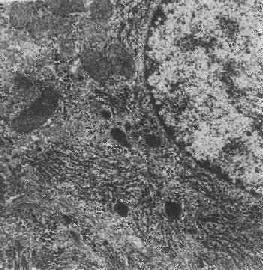

图1-13 初级溶酶体

图中央及中下方之卵圆形电子致密小体,外围单层包膜。(图中及下部片层状膜性结构为粗面内质网(正常肝细胞)